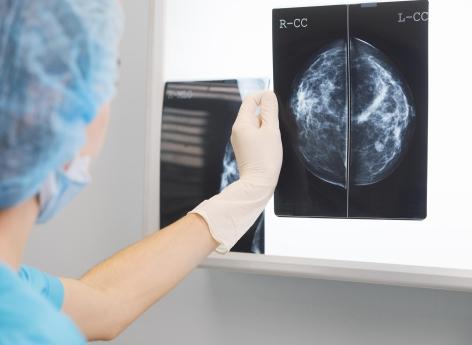

Cancer du sein de Caroline Receveur : qu’est-ce que l’hormonothérapie ?

Suite au diagnostic de son cancer du sein, Caroline Receveur fait actuellement de l’hormonothérapie.

Hier, mercredi 7 février, Caroline Receveur a donné de ses nouvelles sur Instagram. Officiellement en rémission de son cancer du sein, l’influenceuse issue du milieu de la téléréalité doit encore suivre des protocoles de soins.

Cancer du sein : "le plus compliqué, ce sont les douleurs liées à l’hormonothérapie"

"Réveil 5h ce matin et nuit pas du tout réparatrice. Le sommeil est toujours un peu perturbé après l'immunothérapie", raconte-t-elle.

"Le plus compliqué, ce sont les douleurs articulaires liées à l’hormonothérapie. J'ai l'impression d'avoir 85 ans quand je me réveille le matin. J'ai vraiment mal partout", poursuit Caroline Receveur.

"Heureusement, au fil de la journée, les douleurs diminuent et le sport m'aide énormément à relâcher les tensions. Mon oncologue m'a conseillé l'acupuncture (que je faisais beaucoup pendant mon traitement chimio et que j'ai stoppé depuis). Je vais donc reprendre quelques séances", explique-t-elle également.

Après avoir subi une douloureuse mastectomie en novembre dernier, la jeune maman d’un petit garçon de 5 ans a récemment annoncé être en rémission. "Je discutais avec le docteur Wissam et il m’a dit un truc qu’on ne m’avait jamais dit officiellement : je suis cancer free", a-t-elle posté il y a quelque temps sur les réseaux sociaux.

Traitement du cancer : on distingue deux types d'hormonothérapie

Certaines tumeurs du sein ont pour caractéristique d'être hormonosensibles, ce qui signifie que les hormones féminines (œstrogènes/progestérone), naturellement produites par l'organisme, stimulent leur croissance. "L'hormonothérapie est un traitement qui consiste à empêcher l'action stimulante des hormones féminines sur les cellules cancéreuses", explique l’Institut National du cancer.

On distingue deux types d'hormonothérapie :

- les traitements médicamenteux, qui agissent dans l'ensemble du corps sur toutes les cellules sensibles aux hormones. On parle alors de « soin systémique » ;

- les traitements non-médicamenteux, qui consistent à stopper la production d'œstrogènes par les ovaires en les retirant par une intervention chirurgicale (ovariectomie) ou en les irradiant (radiothérapie).

Chaque année, plus de 50.000 femmes développent un cancer du sein en France. Parmi elles, plus de 80 % vivront au-delà de 10 ans après leur maladie grâce aux progrès médicaux et scientifiques.

Cependant, les traitements administrés génèrent souvent des toxicités à plus ou moins long terme. Après un cancer du sein, les patientes peuvent être confrontées à des difficultés dans leur vie quotidienne : modification de l’image du corps, douleurs, fatigue, troubles chroniques des fonctions motrices, problèmes urinaires, conséquences psychologiques, etc...